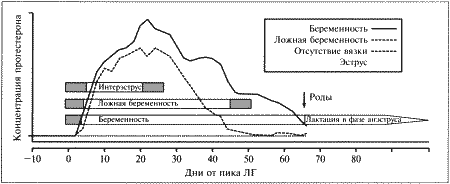

Фиг. 2.1.

Изменения концентрации прогестерона в плазме крови при физиологической и ложной беременности. Воспроизведено из кн. Lane и Cooper «Veterinary Nursing», (1994) с разрешения Butterworth Heinemann

ГОРМОНАЛЬНАЯ ПОДДЕРЖКА ОВУЛЯЦИИ, ЛОЖНАЯ БЕРЕМЕННОСТЬ И БЕРЕМЕННОСТЬ

Инфертильная вязка (без оплодотворения)

При отсутствии оплодотворения яйцеклеток желтые тела развиваются и вырабатывают прогестерон в течение приблизительно 25–45 дней. Эта лютеиновая фаза короче аналогичного периода, наблюдаемого при развитии беременности, потому ее часто называют ложной беременностью. Таким образом, ложная беременность у кошек представляет собой лютеиновую фазу, следующую за овуляцией, которая не завершилась оплодотворением и имплантацией, однако у них — в отличие от собак — не бывает изменений в поведении и лактации. В течение этого периода секреция ГнРГ угнетена, что обеспечивает высокий уровень прогестерона, препятствующий возобновлению течки. Лютеиновая фаза, или ложная беременность завершается коротким интерэструсом, предшествующим возобновлению эструса, если продолжается брачный сезон или наступает фаза анэструса.

Прогестерон

В период анэструса, интерэструса, проэструса и эструса концентрация прогестерона поддерживается на базальном уровне вплоть до овуляции.

У кошек как при беременности, так и в ее отсутствие — концентрация прогестерона в плазме начинает повышаться после овуляции, через 24–50 часов после выброса ЛГ. Максимальные показатели прогестерона (100–200 нмоль/л) наблюдаются на 20–25 день после первой вязки.

При ложной беременности концентрация прогестерона начинает снижаться приблизительно на 25 день и достигает базального уровня на 30–40 день. Такое постепенное снижение концентрации прогестерона является характерной особенностью ложной беременности у кошек. При истинной (физиологической) беременности концентрация прогестерона поддерживается на высоком уровне в течение всего периода вынашивания и стремительно снижается перед родами. Постепенное снижение концентрации прогестерона в конце ложной беременности у кошек сходно с тем, что наблюдается у собак, и, вероятно, объясняется отсутствием лютеолитического фактора, вырабатываемого в организме самок в конце беременности. Очевидно, на 25–35 день ложной беременности желтые тела, лишенные лютеотрофической поддержки со стороны эмбрионов и плаценты, подвергаются «запрограммированной» атрофии. Гистероэктомия, выполненная во время лютеиновой фазы ложной беременности, не отражается на жизнеспособности желтых тел, что свидетельствует о том, что матка не участвует в процессе рассасывания желтых тел.

Снижение концентрации прогестерона начинается на 25–35 день беременности, после чего вплоть до 60 дня ее значения поддерживаются на уровне 15–30 нмоль/л (5–10 нг/мл). Прогестерон необходим кошкам в течение всего срока вынашивания для сохранения беременности, хотя беременность может сохраняться в течение нескольких дней после того, как концентрация прогестерона в плазме крови снижается < 3 нмоль/л (< 1 нг/мл) очевидно, эти показатели являются необходимым минимумом, при котором беременность не прерывается. Основной источник прогестерона — желтые тела. Овариоэктомия на любой стадии беременности приводит к снижению концентрации прогестерона < 3 нмоль/л (< 1 нг/мл) в течение 48 часов после хирургического вмешательства. Плацента либо вырабатывает прогестерон в очень незначительном количестве, недостаточном для сохранения беременности, либо вовсе не участвует в этом процессе.